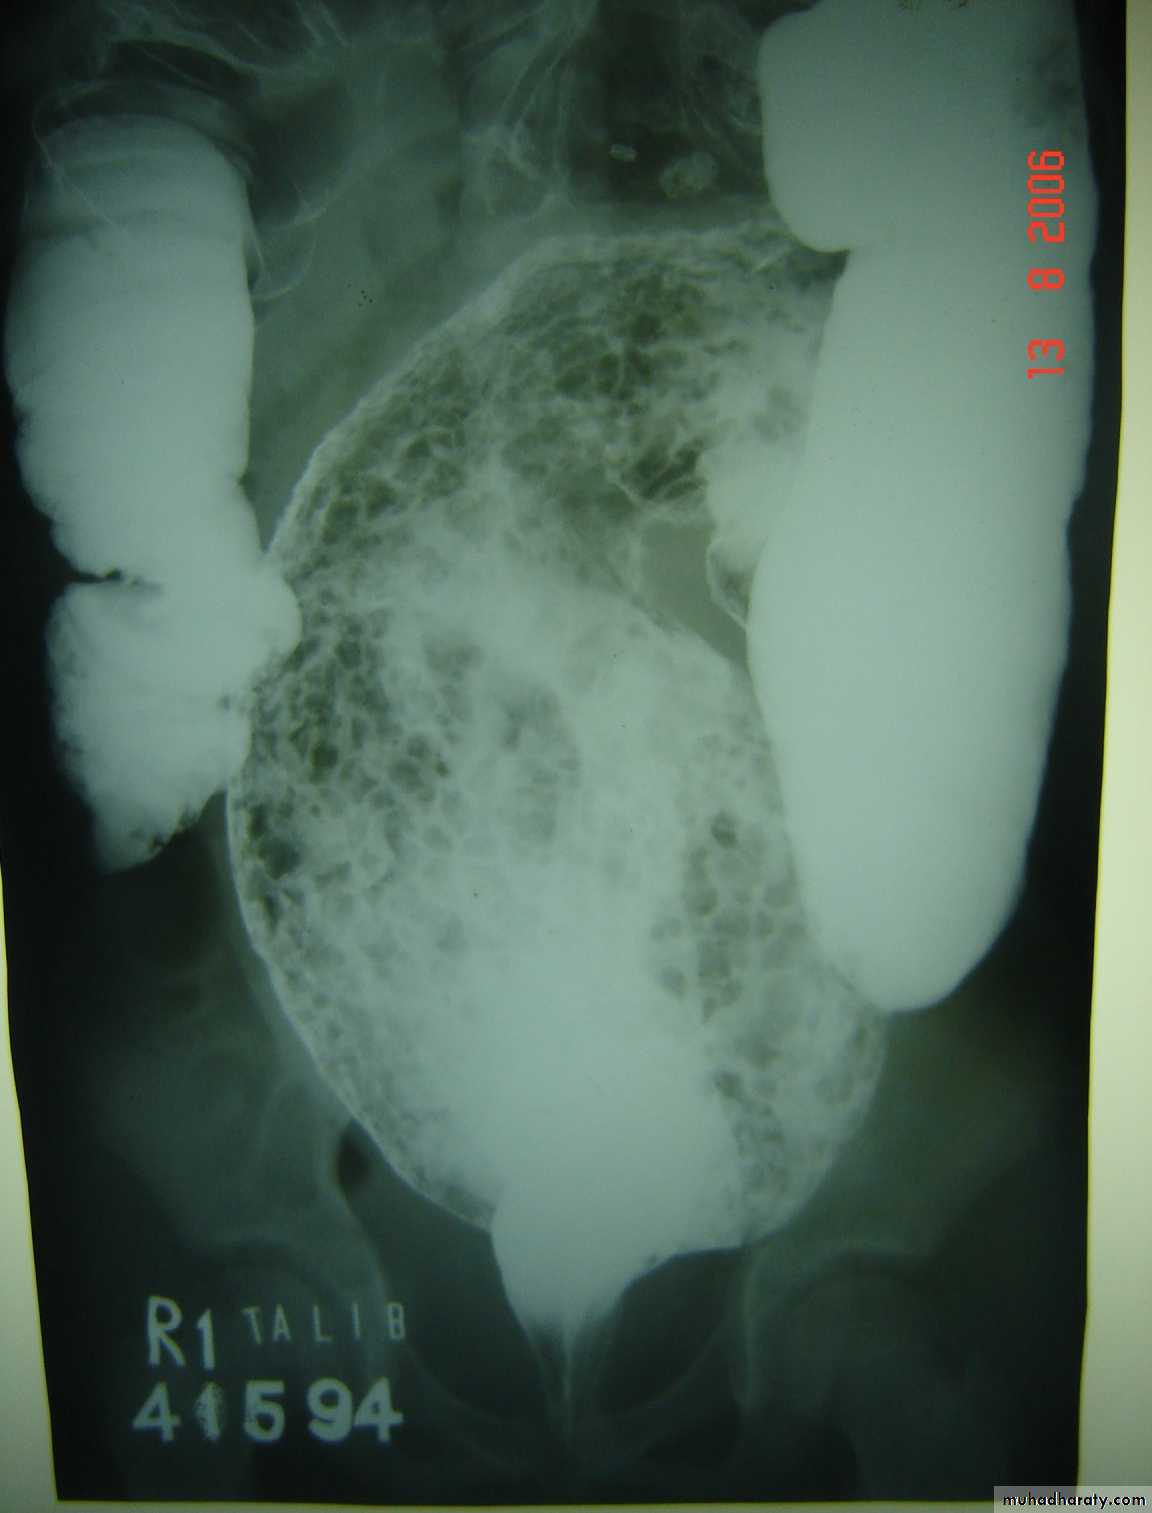

N.E.C

Tutorial